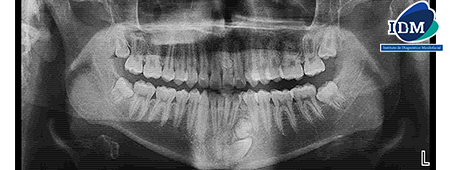

Radiografia Panorámica

En la radiografía panorámica se observan imágenes radiopacas de densidad dentaria proyectadas sobre la pieza 21 y entre las raíces de las piezas 34 y 32. La persistencia de la pieza 73 y la localización ectópica de la pieza 33.